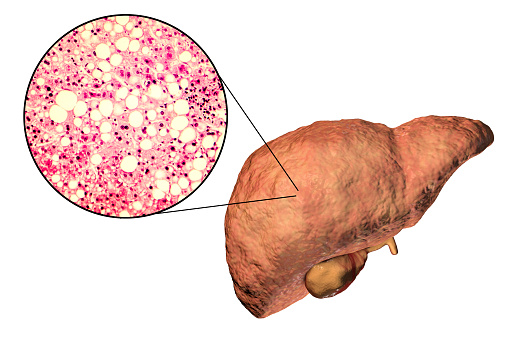

Alcoholism is an ever growing problem faced by societies throughout the world. About 86 percent of Americans over the age of 18 reported drinking at some point in their lifetime. Alcohol Awareness Month, held on April of every year, aims at increasing awareness about its causes, treatment, and recovery. This year the theme is “Changing ...click here to read more